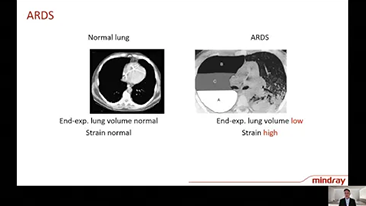

La scelta delle impostazioni corrette del ventilatore per il trattamento dei pazienti con malattie delle vie respiratorie Ú una questione piuttosto importante. Poiché il compito di specificare i parametri delle apparecchiature di ventilazione Ú interamente svolto dal medico, la conoscenza e l'esperienza di quest'ultimo nella selezione di tali impostazioni ha un effetto diretto sull'accuratezza delle sue decisioni. Il paradigma delle terapie di supporto Ú cambiato in modo significativo negli ultimi 20 anni. Al giorno d'oggi, diverse modalità di ventilazione e strumenti di supporto per il processo decisionale sono state sviluppate in base alle esigenze cliniche per aiutare gli operatori a migliorare l'efficienza e a evitare errori nelle decisioni cliniche.